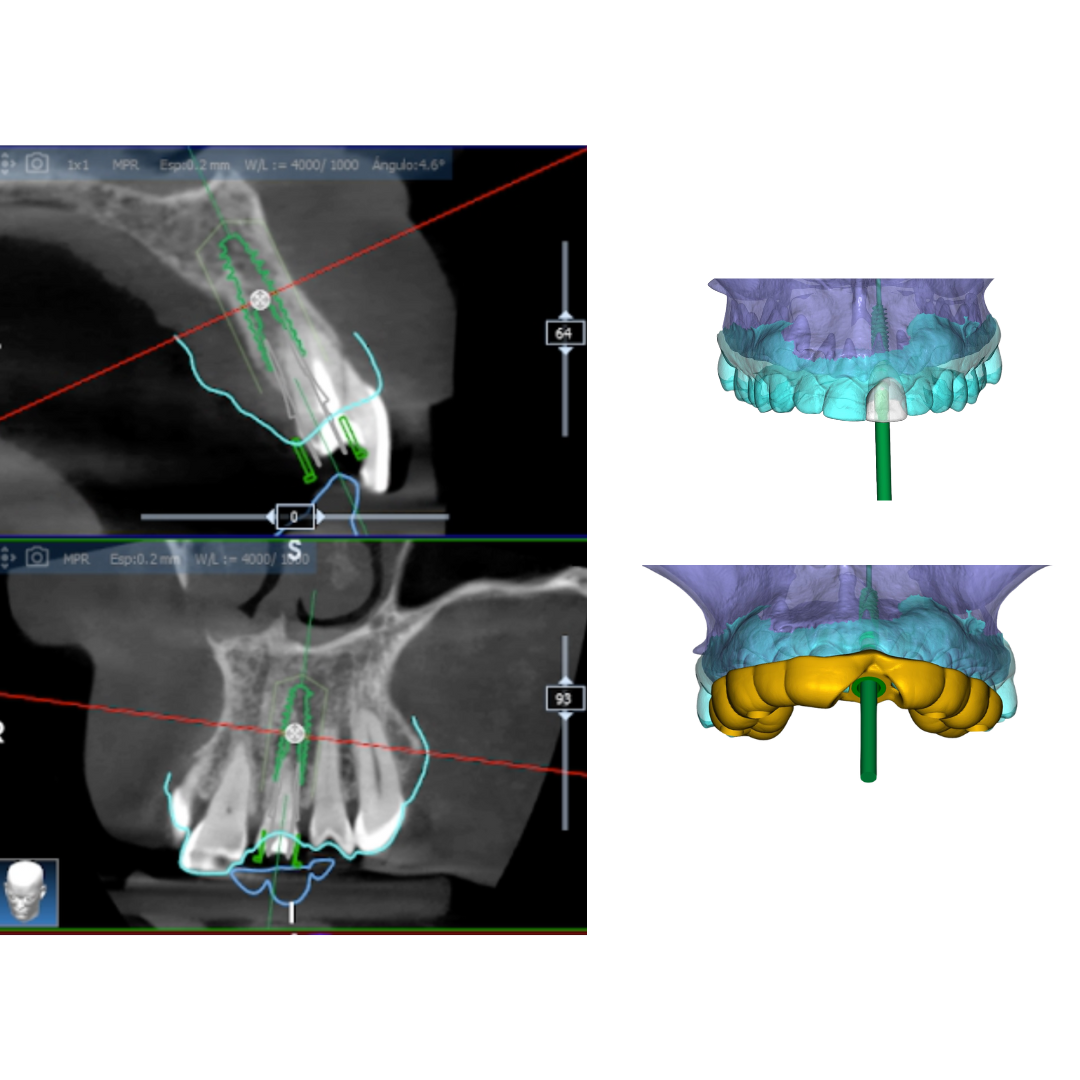

We place implants using guided surgery

This digital planning reduces error margins and enables minimally invasive surgery without extensive incisions. This translates to shorter intervention times, faster recovery, and a more comfortable experience for the patient.

Unlike conventional surgery, guided surgery optimises precision and reduces risks, allowing us to place implants with maximum safety and efficiency. With this technology, we achieve predictable and aesthetic results, ensuring functionality and well-being from day one.